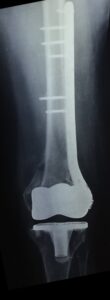

- Περιπροθετικό κάταγμα λίγο πιο κεντρικά από το πέρας του εμφυτεύματος του γόνατος

- Ευθυγράμμιση του οστού και η οστεοσύνθεση με ειδική πλάκα τιτανίου και κλειδούμενους κοχλίες.